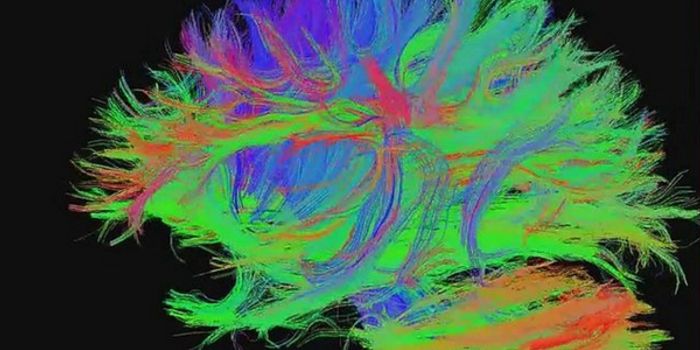

Read the latest articles about newly released neuroscience research and advances in experimental techniques. Topics include research news in neuroscience, neurology, psychology, brain science and cognitive sciences.